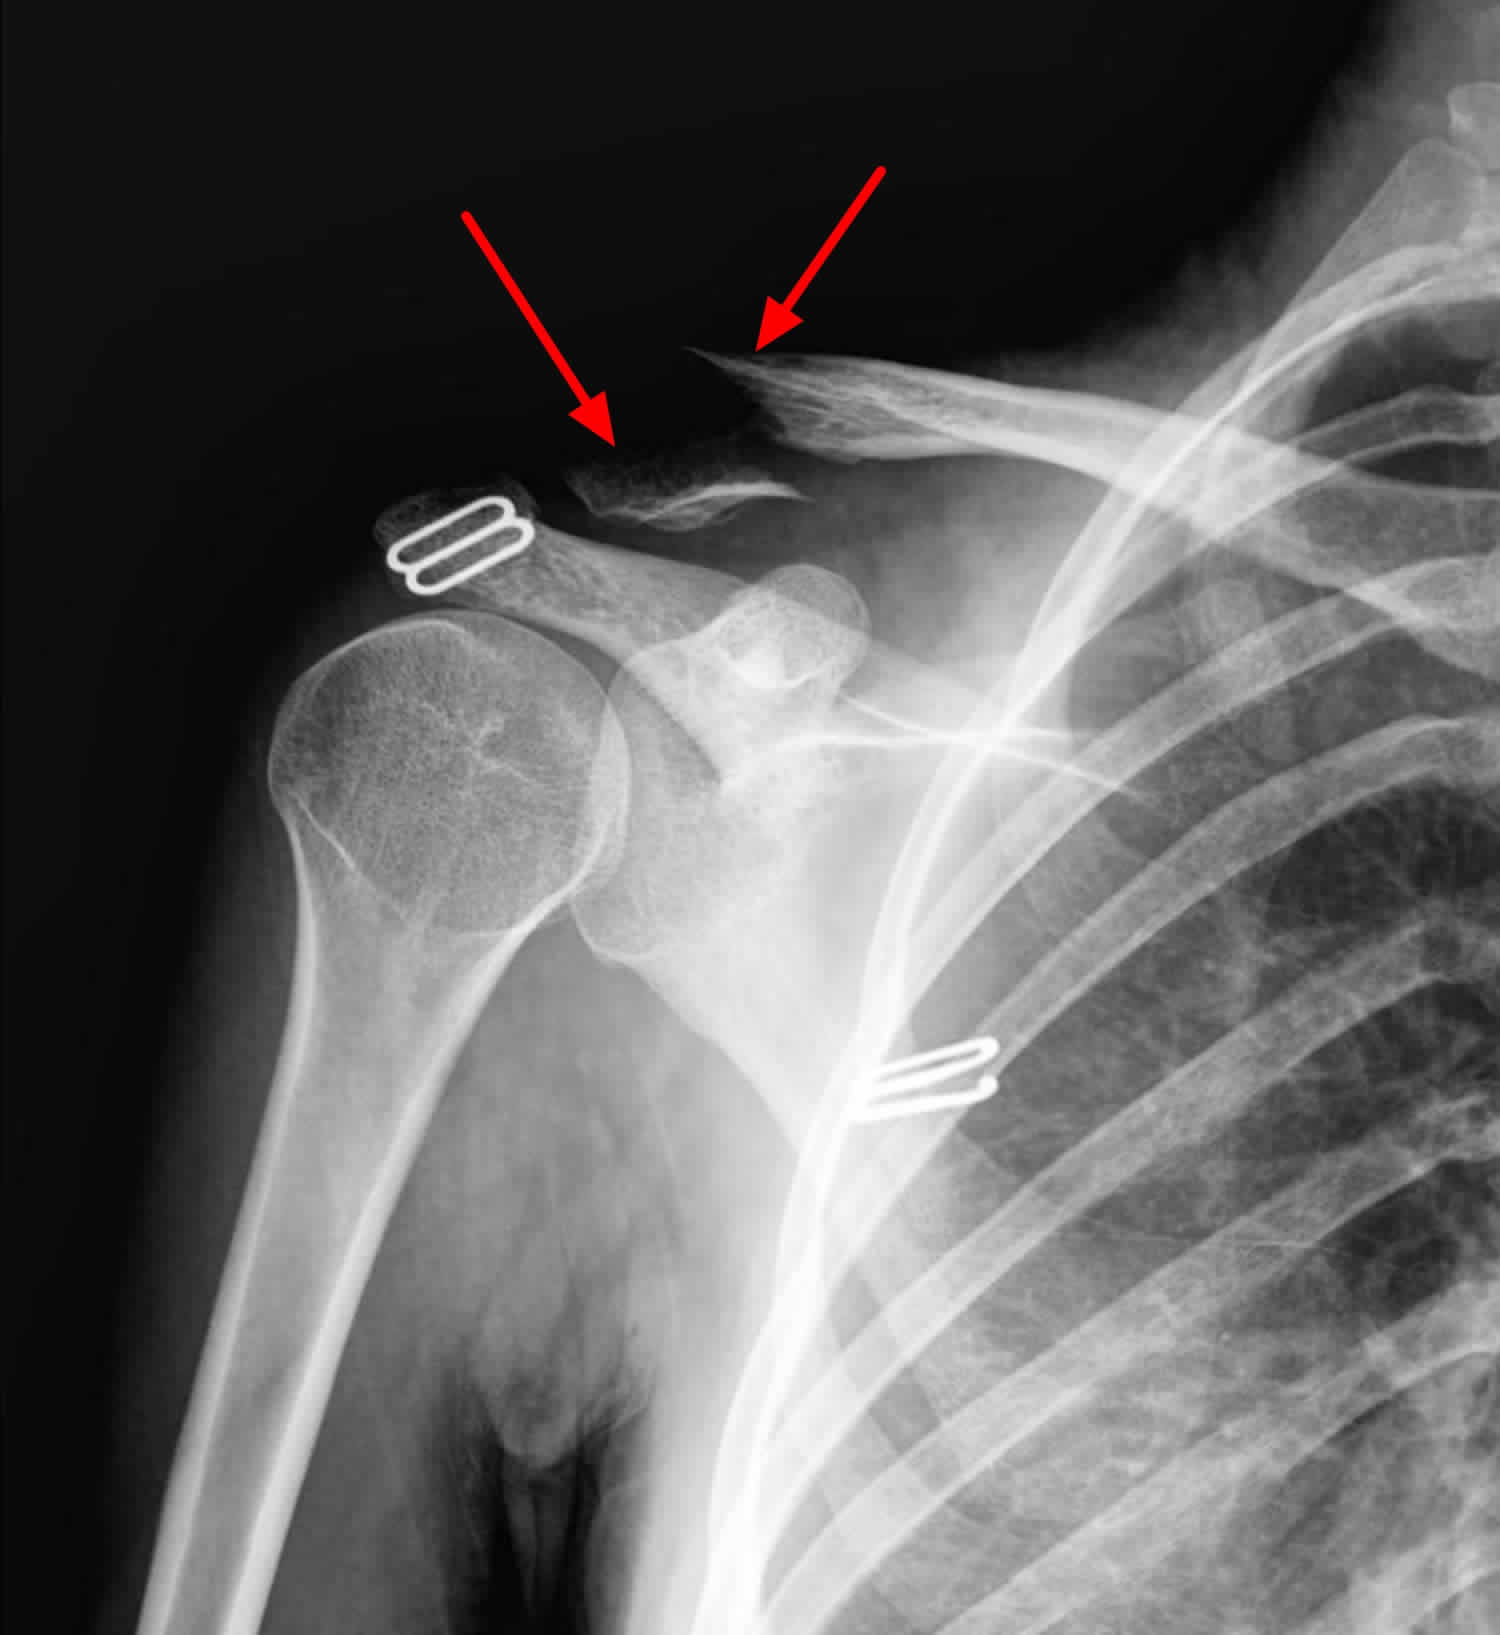

Can You Move Your Shoulder With A Broken Collarbone . You might be able to move your shoulder if it’s fractured, but it’ll probably be painful. Most collarbone fractures heal on their own with conservative. Once the break has healed, your doctor or physical therapist can give you exercises to strengthen your shoulder. Can you move your shoulder if it’s fractured? With some clavicle fractures, however, the pieces of bone move far out of place when the injury occurs. While your broken collarbone is healing, you might not be able to lift heavy things or move your shoulder fully. You may move your elbow, hands, and fingers as it becomes comfortable to do so. A clavicle fracture aka broken collarbone is a common shoulder injury. A broken collarbone can be very painful and can make it hard to move your arm. A fall or a blow to your shoulder can fracture your collarbone (clavicle). This can be due to pain or your. Many clavicle fractures can be treated by wearing a sling to keep the arm and shoulder from moving while the bone heals. We look at symptoms, causes and treatment including top tips on making a full recovery You can move your arm and shoulder without any pain.

A fall or a blow to your shoulder can fracture your collarbone (clavicle). You can move your arm and shoulder without any pain. You might be able to move your shoulder if it’s fractured, but it’ll probably be painful. A broken collarbone can be very painful and can make it hard to move your arm. Most collarbone fractures heal on their own with conservative. This can be due to pain or your. With some clavicle fractures, however, the pieces of bone move far out of place when the injury occurs. Many clavicle fractures can be treated by wearing a sling to keep the arm and shoulder from moving while the bone heals. Once the break has healed, your doctor or physical therapist can give you exercises to strengthen your shoulder. While your broken collarbone is healing, you might not be able to lift heavy things or move your shoulder fully.